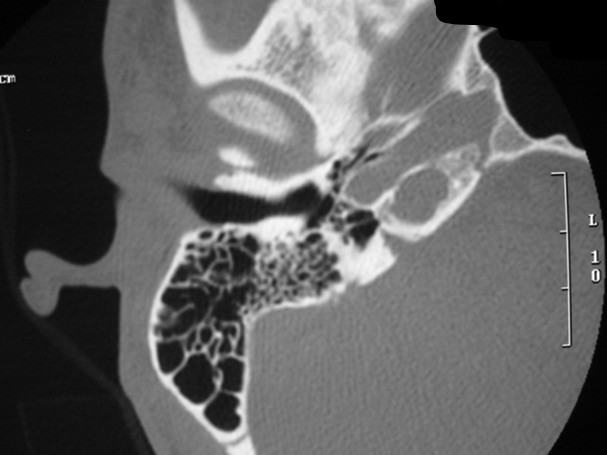

The petrous apex is a relatively inaccessible area that can occasionally harbor serious disease. Disease processes that usually cause symptoms are typically inflammatory or neoplastic in nature. Petrous apex lesions typically cause nonspecific symptoms such as headache, but as the lesion becomes more extensive, adjacent structures such as cranial nerves can become involved. A common early and specific sign of a petrous apex process is abducens palsy. Current imaging techniques can usually provide enough supplemental information to allow a focused plan of treatment. It is important to determine whether a petrous apex lesion can be observed or, if surgical treatment is required, whether a drainage or excision is required. There are various available surgical approaches to the petrous apex. The choice depends on the status of hearing function as well as the suspected pathology, which will dictate whether a drainage or excisional procedure is required.

- Summarize the types of pathology that can occur in the petrous apex, the imaging required, and proper interpretation of information so that a proper differential diagnosis can be formulated.